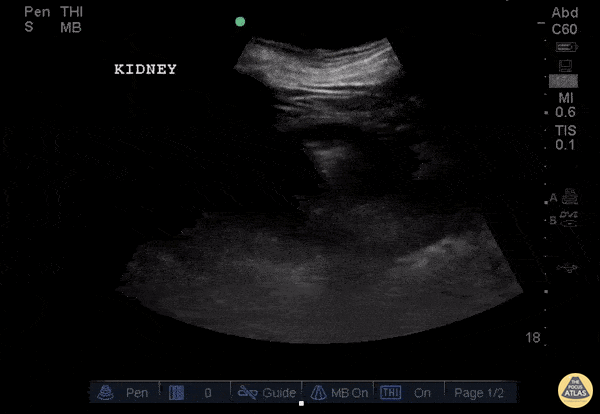

This clip demonstrates air within the parenchyma of the kidney consistent with emphysematous pyelonephritis. This is different than emphysematous pyelitis in which air is only seen in the collection system. Image courtesy of Robert Jones DO, FACEP @RJonesSonoEM Director, Emergency Ultrasound; MetroHealth Medical Center; Professor, Case Western Reserve Medical School, Cleveland, OH View his original post here